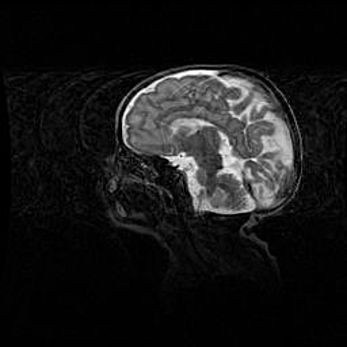

Неполная лизэнцефалия (пахигирия). Открытая гидроцефалия.

Возраст: 17 дней

Вес: 3110 г

Пол: мужской

Окружность головы: 33,5 см

Срок гестации: 35-36 недель

Лизэнцефалия—недоразвитие корковой пластинки и мозговых извилин в результате нарушения миграции нейронов коры. Поверхность мозговых полушарий гладкая. Микроскопически выявляется отсутствие нормальных слоев коры и скопление групп нейронов в подкорковом белом веществе.

Пахигирия—уменьшение числа вторичных извилин. В пораженном полушарии нервные клетки образуют толстый недифференцированный слой с неправильно расположенными нервными волокнами и группами гетеротопных клеток. Нервные клетки незрелые. Белое вещество истончено. При этом нередко аномально развит корково-спинномозговой путь.